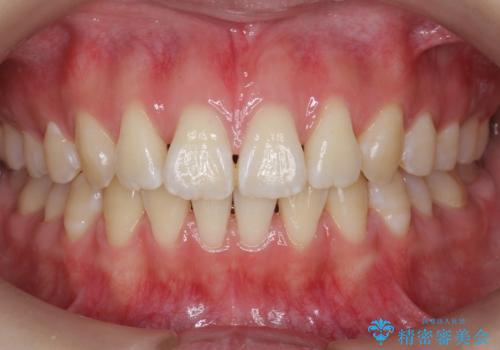

![[ インビザライン矯正 ] マウスピース矯正で治す、前歯のガタつきの症例 治療前](https://seimitsushinbi.jp/wp/wp-content/uploads/2022/02/324533f54aaa29eca08b0a9fdd3af7e2-500x350.jpg?v=1644473292)